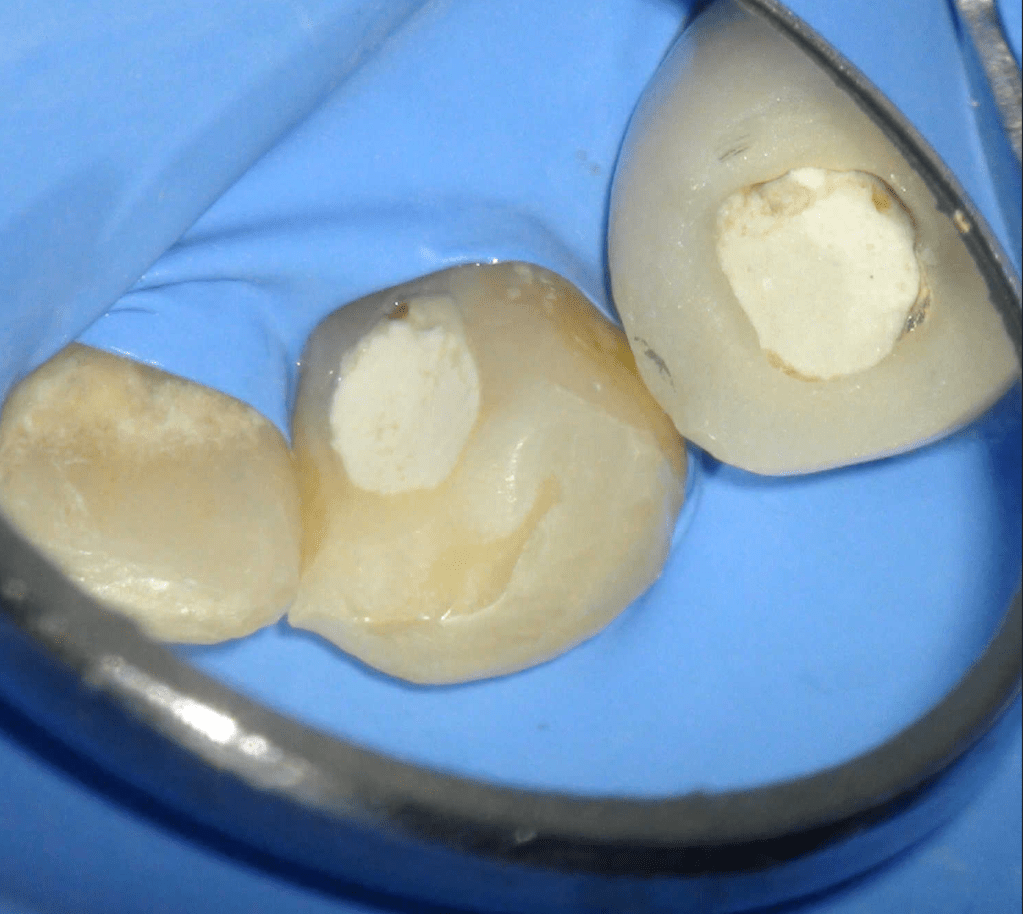

Molar superior

Reco palatina

Reco pared vesticular

Reco pre-endo gingivectomái, pared yuxtaosea

Reco pre-endo, molar inferior

Reco preendo + 4 conductos molar superior

Reco preendo + gingivectomía

Reco preendo, 2o Molar superior

Reconstrucción debajo de puente